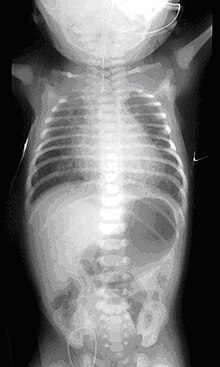

Ребенок (девочка), П, 1 мес 16 дн., находилась на стационарном лечении в Научно-клиническом отделе детской оториноларингологии с 30.06.2015 по 13.07.2015 г. с основным клиническим диагнозом: Врожденная двусторонняя полная костная атрезия хоан. Сопутствующий диагноз: Перинатальное поражение ЦНС. Синдром тонусных нарушений. МАРС. Анемия легкой степени.

Из анамнеза известно, что указанные жалобы беспокоят с рождения. Ребенок родился в срок 40-41 неделя (27.05.2015), на фоне нарастания дыхательной недостаточности, через два часа после родов проведена интубация трахеи. Экстубация трахеи — 29.05.2015. С 01.06.2015 по 20.06.2015 с диагнозом нижнедолевая сегментарная правосторонняя пневмония, пиодермия, ринит, конъюнктивит девочка была на стационарном лечении в ОГБУЗ «Детской областной клинической больницы» г. Белгород. Проведено СКТ: картина двусторонней атрезии хоан. Рекомендовано консультация в НКЦО г. Москва. Ребёнок консультирован проф. Юнусову А.С. 22.06.2015 г. и направлен на хирургическое лечение в Отдел детской ЛОР патологии ФГБУ НКЦО ФМБА России.